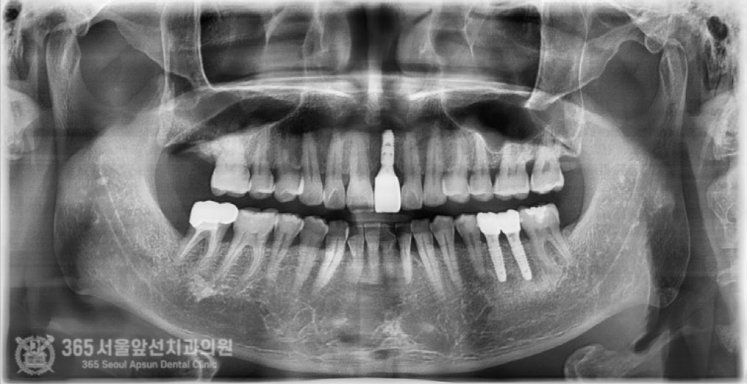

몸에서 냄새가 나고 고름이 나오다가 이제는 저절로 빠질 것 같아요... 안녕하세요. 도화역치과 365서울앞선치과의원입니다. 오늘은 심한 풍치를 앓던 앞니 임플란트 치료증례를 살펴보겠습니다. 이 환자분은 저와 특별한 사연이 있는 환자분이십니다. 바로 제가 일하던 치과의 소독실 전담 선생님의 남편분이신데요. 이렇게 가까이서 소통하던 직원분들도 가족의 치료를 믿고 맡겨주니 기대에 부응하기 위해 책임감을 막중히 느낍니다 ㅎㅎ 촬영일시 : 2024.07.02. 처음 내원당시 엑스레이 사진입니다. 왼쪽 앞니가 많이 안좋아 보입니다. 심한 풍치로 인해 잇몸뼈가 거의 다 없어졌고 치아가 저절로 빠질 정도로 흔들린다고 하셨습니다.

촬영일시 : 2024.07.02. 풍치로 인한 염증 부위를 색상으로 표시해보았습니다. (노란색) 3차원 CT를 이용하여 분석해보니 잇몸뼈가 염증으로 인해 녹은 상태로 매우 심각했습니다.....ㅠㅠ 촬영일시 : 2024.07.02. 결국 해당 치아는 발치를 하게 되었고, 임플란트 식립과 동시에 염증으로 인해 없어진 뼈를 재건하는 골이식을 시행하게 되었습니다. 발치를 하고 나서 임플란트 식립 및 골이식 수술 전 확인해보니 염증으로 소실된 뼈가 상당합니다. 촬영일시 : 2024.07.02. 임플란트를 식립했고 그 위로 두툼하게 골이식을 시행합니다. 일반적으로 골이식은 흡수되는 양이 상당합니다. 그래서 앞니 부위와 같이 미적으로 중요한 부위에서는 자연스러운 잇몸의 볼륨을 위해서 흡수되는 양을 감안하여 많은 양의 골이식을 시행하고있습니다. 임플란트를 식립 후에는 보통 작은 임시틀니를 드리고 그걸 사용하시는 경우가 많은데요. 지금처럼 골이식이 많이 들어간 경우에는 임시틀니를 사용할 경우 이식한 뼈가 제대로 성숙되지 못하는 경우가 많기에 다른 방식의 임시치아를 해드리고 있습니다. 위 환자분께서도 붙이는 형태의 임시치아를 해드렸고 잘사용하셨습니다. 촬영일시 : 2024.11.01. 4개월이 지나서 임플란트가 뼈와 잘 결합되었구요. 이식한 뼈도 단단해졌기에 슬슬 본 뜰 준비를 해봅니다. 동그랗게 회색 단추가 달려있는데요. 치유지대주라고 부르는 구조물로 이걸 이용하여 본을 뜨게 됩니다. 촬영일시 : 2024.11.05. 완성된 최종 보철물입니다. 사실 중간에 임플란트와 연결된 임시치아를 사용하여 잇몸 모양을 잡아주는 과정을 거쳤는데요. 아쉽게도 해당 과정에 대한 사진이 없군요 ㅠㅠ 이렇게 섬세하고 복잡한 과정을 거쳐서 임플란트 치료가 마무리 되었습니다 ㅎㅎ 이식된 뼈 부위도 통통하게 뼈가 잘되어있습니다 ㅎㅎ 만족스럽습니다. 촬영일시 : 2024.11.05. 치료가 마무리 된 후 엑스레이 사진입니다. 최종 보철물 장착 완료까지 자연스럽게 잘 마무리되어 기분이 좋네요. 직원분께서 가족의 치료를 믿고 맡겨주셨고, 그에 보답할 수 있어 기분 좋은 치료 증례였습니다. 앞으로도 더 유익한 치료 증례로 찾아뵙겠습니다. 도화역치과 365서울앞선치과의원이었습니다. 감사합니다. [ 치료기간: 2024년 7월2일 ~ 2024년 11월 5일 ] ※ 365서울앞선치과의원의 모든 포스팅은 각 진료과 의료진이 직접 작성합니다. 365서울앞선치과의원 블로그의 임상 케이스 게시물은 환자분께 의학적으로 정확하고 상세한 정보를 드리기 위해 각 진료과 의료진이 직접 작성하며, 모든 증례 사진은 본원 의료진이 직접 시술한 증례를 촬영한 것으로, 의료법 제23조, 제56조에 의거하며 환자분의 동의를 얻어 포스팅에 사용하였습니다. 또한 해당 케이스는 본 환자분의 치료 결과이며, 환자 상태에 따라 치료의 결과는 달라질 수 있습니다. |